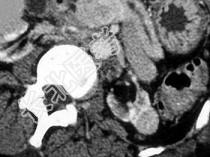

- 单项选择题患者长期透析,根据所提供的图像, 最可能的诊断是 ( )

A、肾囊肿出血

B、肾癌

C、转移癌

D、良性肿瘤

E、以上都不是